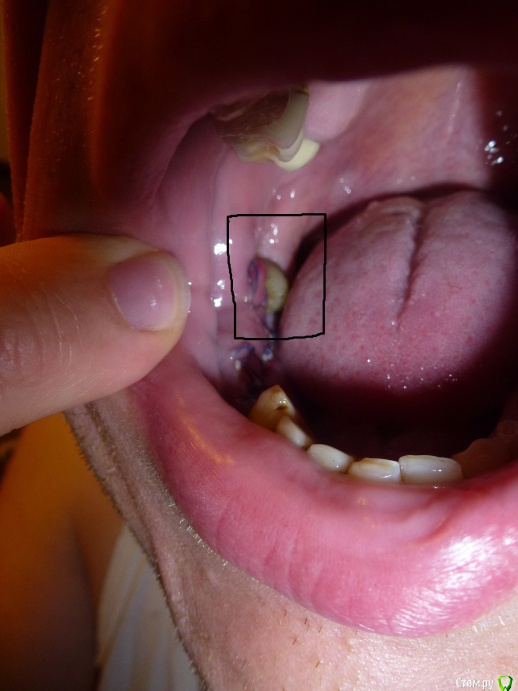

Новичок - СПБ Опубликовано 14 июня, 2015 Поделиться Опубликовано 14 июня, 2015 (изменено) Здравствуйте!Прошу Вас дать консультацию по моему вопросу:Четыре дня назад делал операцию по пересадке костного трансплантата. После операции возникли болеевые ощущения во внутренней части щеки.Посветив фонариком обнаружил,что в том месте где проводилась операция,после наложения швов, щека начала наваливаться на восьмой зуб. Более того она оголенна!При приёме пищи возникают болевые ощущения и жуткий дискомфорт.Получается я кусаю собственную щеку во время приёма еды. вопрос: Что делать??? Боль в данном месте проходит только после приёма обезболивающих препаратов. Буду признателен за высказанное мнение. Изменено 14 июня, 2015 пользователем Новичок - СПБ Ссылка на комментарий

Новичок - СПБ Опубликовано 15 июня, 2015 Автор Поделиться Опубликовано 15 июня, 2015 не жевать там, отек пойдет на спад и все пройдет. Ждите.Отёк уже прошёл,а щека как налегала на зуб так и налегает. Ссылка на комментарий

Bier Опубликовано 15 июня, 2015 Поделиться Опубликовано 15 июня, 2015 отек еще не спал, прошло всего 4-5 дней. Ждите 2 недели.Чтобы ушить подсаженную кость лоскут тянется со щеки, разумеется он наползет на зуб. 1 Ссылка на комментарий